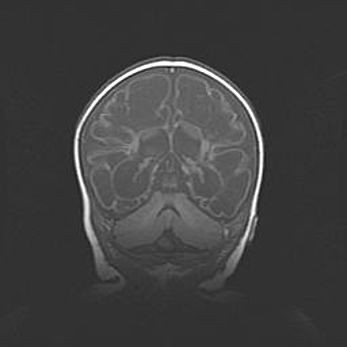

Неполная лизэнцефалия (пахигирия). Открытая гидроцефалия.

Возраст: 17 дней

Вес: 3110 г

Пол: мужской

Окружность головы: 33,5 см

Срок гестации: 35-36 недель

Лизэнцефалия—недоразвитие корковой пластинки и мозговых извилин в результате нарушения миграции нейронов коры. Поверхность мозговых полушарий гладкая. Микроскопически выявляется отсутствие нормальных слоев коры и скопление групп нейронов в подкорковом белом веществе.

Пахигирия—уменьшение числа вторичных извилин. В пораженном полушарии нервные клетки образуют толстый недифференцированный слой с неправильно расположенными нервными волокнами и группами гетеротопных клеток. Нервные клетки незрелые. Белое вещество истончено. При этом нередко аномально развит корково-спинномозговой путь.